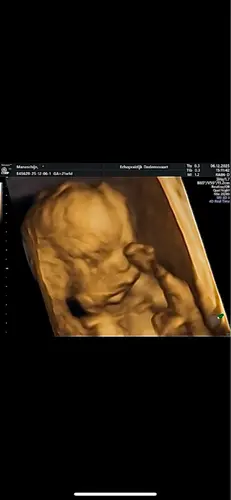

3D echo 馃┑

Gisteren jou mogen bewonderen in 3D!馃槏 En wat was dat bijzonder en mooi om te zien! Iets wat je maar 茅茅n keer kan doen en voor altijd mooie beelden van ons eerste kindje! Met 27 weken gaan we gewoon weer kijken naar jou馃グ Helemaal verliefd op jou!馃┑

Wauw wat mooi! Hoeveel weken is dit? 馃┑

Dankje! 21+1 weken was dit